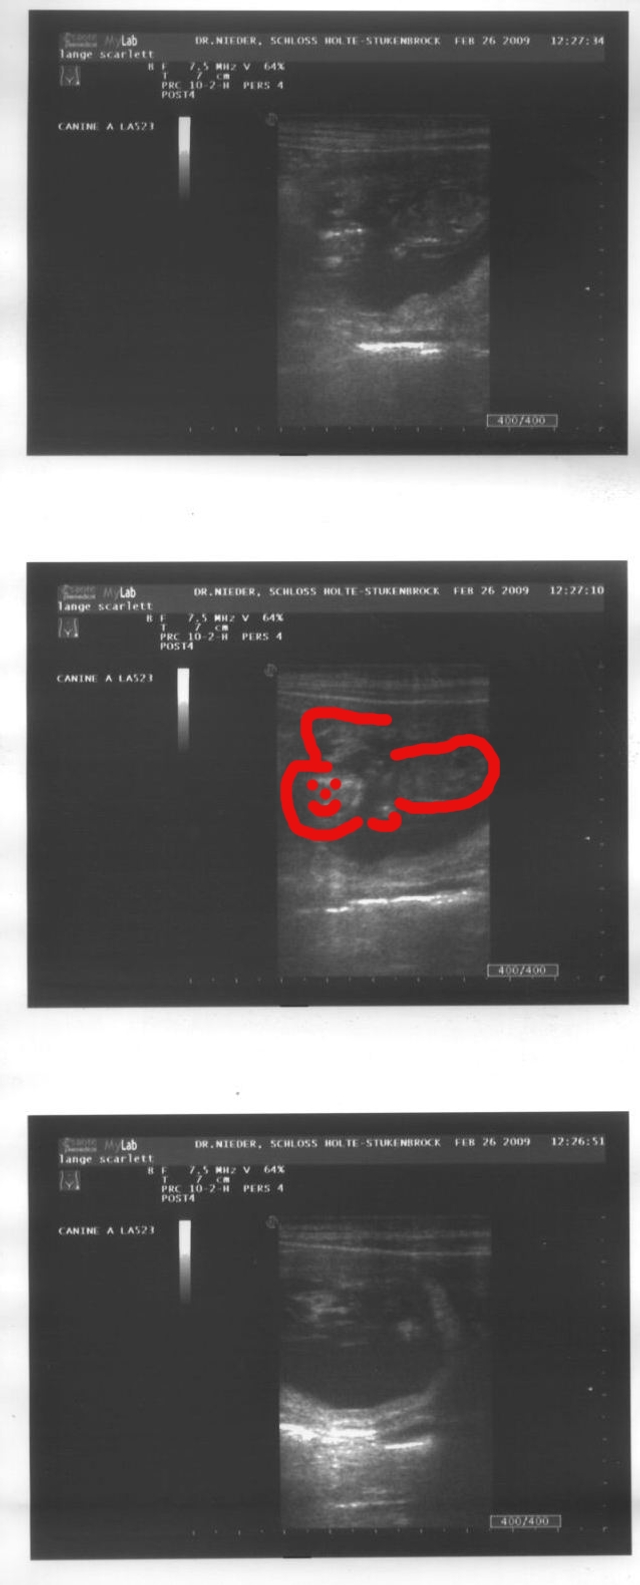

Halleluja, es wird ein Golden Retriever! Donnerstag war Silke bei Frau Dr. Nieder zum Ultraschall. Nein, nicht Silke, sondern Scully - folgend die Beweisfotos:

ultraschall20090226b.jpeg

Ein Baby ganz allein - es schwimmt durch die unendlichen Träume in Scullys Bäuchlein, bis es eines Tages in unser greifbares Leben hinausgespült wird, um mit uns zu spielen, kuscheln, weiterzuträumen. Wir sind ganz gespannt. Morgen bauen wir die Wurfkiste für unseren ersten Retrieverwurf.